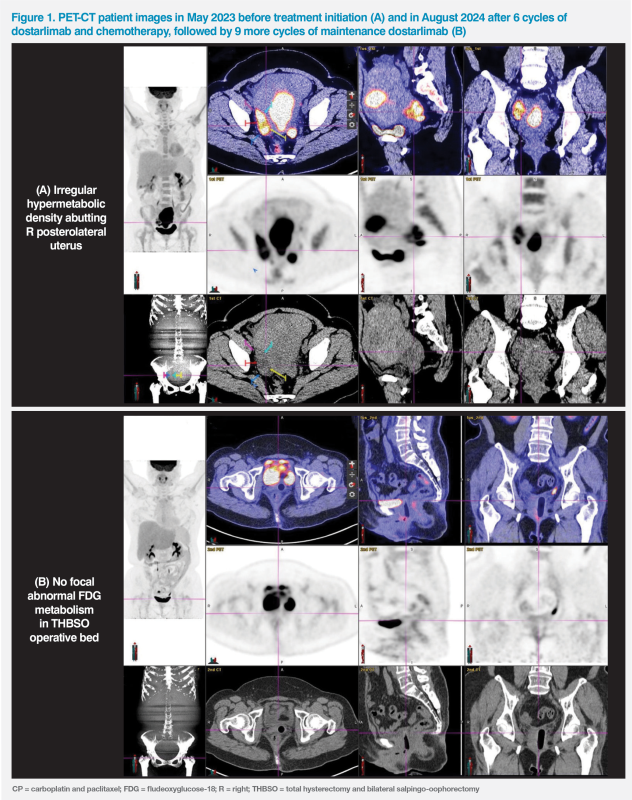

Endometrial aspiration biopsy revealed grade 1 endometrioid adenocarcinoma. A subsequent PET-CT scan showed a large 13.5 x 6.5 cm hypermetabolic mass at endometrium with early myometrial invasion, compatible with uterine malignancy; extra-uterine 18F-FDG uptake in the posterolateral aspect of uterus and pelvic side wall, indicating metastatic disease; nonspecific uptake at abdominal lymph nodes (LNs) was noted. (Figure 1A)

She experienced grade 1 neuropathy while on chemotherapy and grade 1 diarrhoea after RT. A progress scan after completion of the last cycle of chemotherapy in August 2024 showed a clean tumour bed with no tumour recurrence. (Figure 1B)